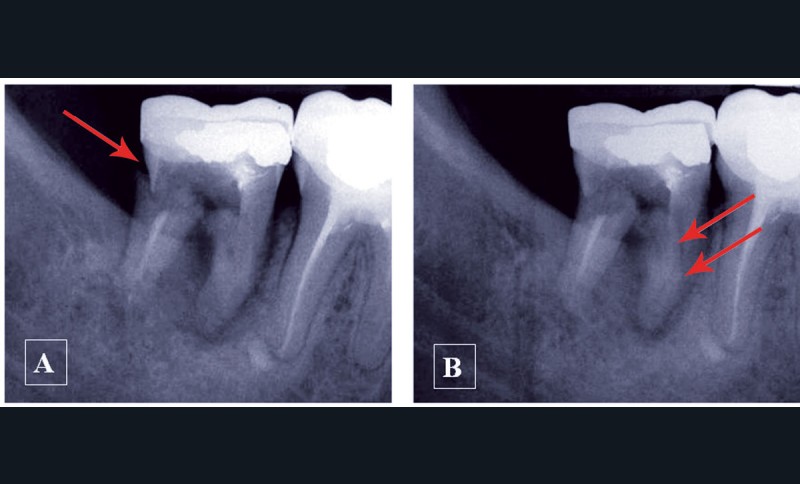

– pour sa forme suivant l’orthogonalité ou l’obliquité du rayonnement par rapport au récepteur (fig. 1).

Une structure anatomique n’est radiologiquement visible que si le rayon directeur (axe du faisceau Rx incident) est tangent à cette structure. Une fracture radiculaire longitudinale ne sera mise en évidence qu’aux conditions d’une orientation favorable et de dimensions suffisantes (fig. 2).